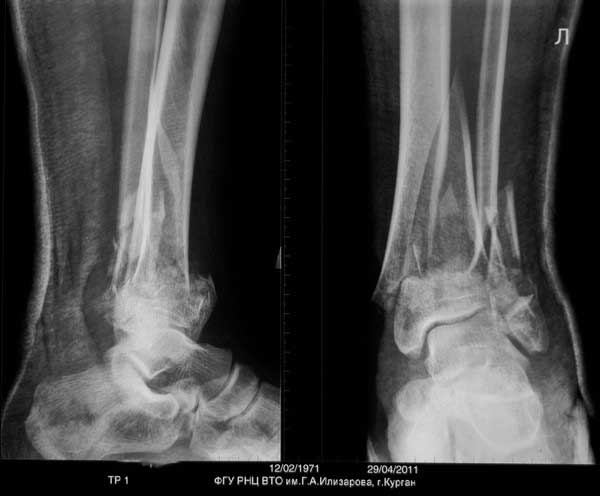

Спасибо уважаемому Джолдасу за ссылку на мою грешную личность. Мое мнение следующее. Уважаемый Сергей! Если Вы хорошо владеете методом чрескостного остеосинтеза, то можете приступать к делу не задумываясь. На рентгеновских снимках созерцаю картину, из которой можно получить наилучший результат именно внешним остеосинтезом. Слова типа "собирать аппарат нудно и т.п", наверное, не совсем к месту. Подарите человеку полное здоровье и, как говорил ныне покойный Леонид Ильич, Вы получите чувство глубокого удовлетворения. И уважения. В данном случае травматичные методы вмешательства могут весьма негативно сказаться на, и так подорванных, остеогенных потенциях тканей и иметь непредсказуемые последствия. А еще лучше - пришлите пациента к нам в Курган. Обещаем выставить результаты лечения на всеобщее обозрение.

Выставляю случай не менее тяжелый. Фиксация в аппарате Мацукидиса-Шевцова 83 дня, общий срок нетрудоспособности 112 дней. Никаких проблем с остеосинтезом и с последующим лечением не было. Никаких воспалений мягких тканей. 3 перевязки за весь период лечения.Главное - захотеть.